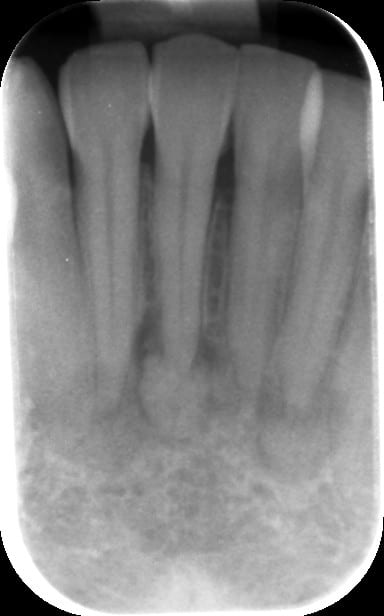

A la rétro alvéolaire on a une image de calcification apicale.

J'ai fait réaliser un CBT et le radiologue me parle de cimentoblastome (je pense cementoblastome).